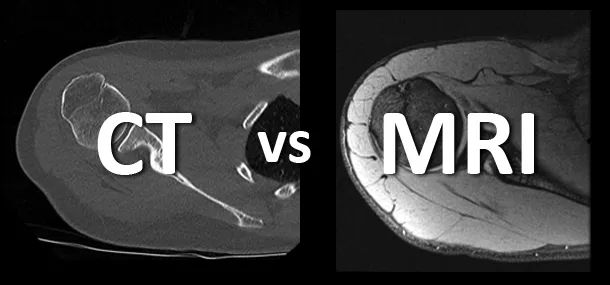

除了PET/CT,還出現了 PET/MRI 等應用。但無論哪種融合,這些融合機型的本質仍為PET, CT和MRI僅是為了彌補PET解剖的不足,使其功能更加完美。